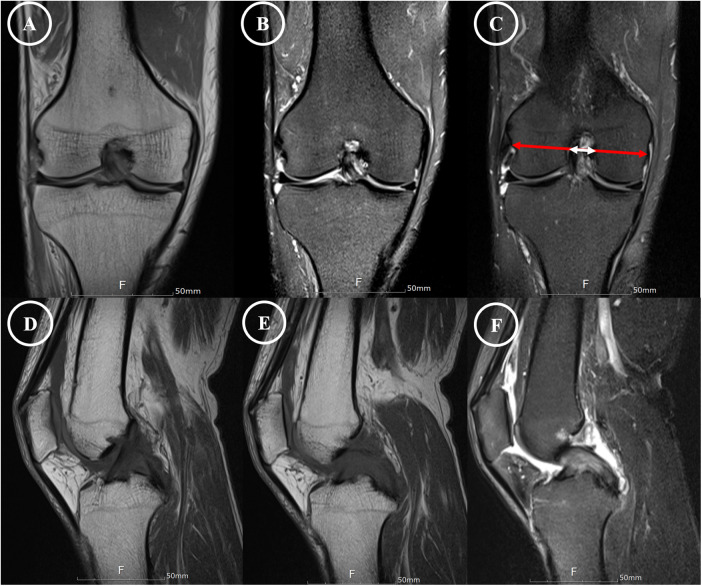

交叉韧带的黏液变性是一种罕见且常被忽视的慢性膝关节疼痛和运动受限的原因。我们报告的情况下,62岁的男子有8年的历史不适,进行性屈曲挛缩,并限制活动范围在右膝。之前在其他地方进行的两次关节镜检查未能确定原因。磁共振成像采用1.5-Tesla扫描仪,切片厚度为3mm,显示前、后交叉韧带弥漫性,韧带内信号增加,纤维完整,与“芹菜茎”征一致。关节镜检查通过标准的前外侧和前内侧门显示两个十字韧带肥大,淡黄色组织。每个韧带大约50%的体积被切除,保留了剩余的完整纤维以保持稳定性。组织学检查证实粘液变性,无炎症浸润。术后6个月,患者实现完全伸展,屈曲度提高至130°,疼痛完全缓解,无临床不稳定。本病例强调了在排除常见关节内病变的情况下,将同时发生的前交叉韧带和前交叉韧带黏液变性作为难愈性膝关节僵硬患者的潜在诊断的重要性。

Mucoid degeneration of the cruciate ligaments is an uncommon and often under-recognized cause of chronic knee pain and motion limitation. We report the case of a 62-year-old man with an eight-year history of discomfort, progressive flexion contracture, and restricted range of motion in the right knee. Two prior arthroscopies performed elsewhere failed to identify the cause. Magnetic resonance imaging using a 1.5-Tesla scanner with 3-mm slice thickness demonstrated diffuse, increased intraligamentous signal with intact fibers in both the anterior and posterior cruciate ligaments, consistent with the "celery stalk" sign. Arthroscopy through standard anterolateral and anteromedial portals revealed hypertrophic, yellowish ligament tissue in both cruciates. Approximately 50% of the bulk of each ligament was resected with preservation of the remaining intact fibers to maintain stability. Histologic examination confirmed mucoid degeneration without inflammatory infiltration. At six months postoperatively, the patient achieved full extension, improved flexion to 130°, and complete resolution of pain, without clinical instability. This case emphasizes the importance of considering simultaneous ACL and PCL mucoid degeneration as a potential diagnosis in patients with refractory knee stiffness when common intra-articular pathologies have been excluded.